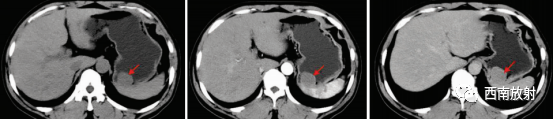

▲病例 间质瘤:男,49 岁,查体发现胃占位性病变 。分别为CT平扫、动脉期及平衡期示胃底处一类圆形软组织结节(箭头),大小约29 mm×28 mm,边界清晰,密度均匀,增强扫描均匀轻度强化[4]。